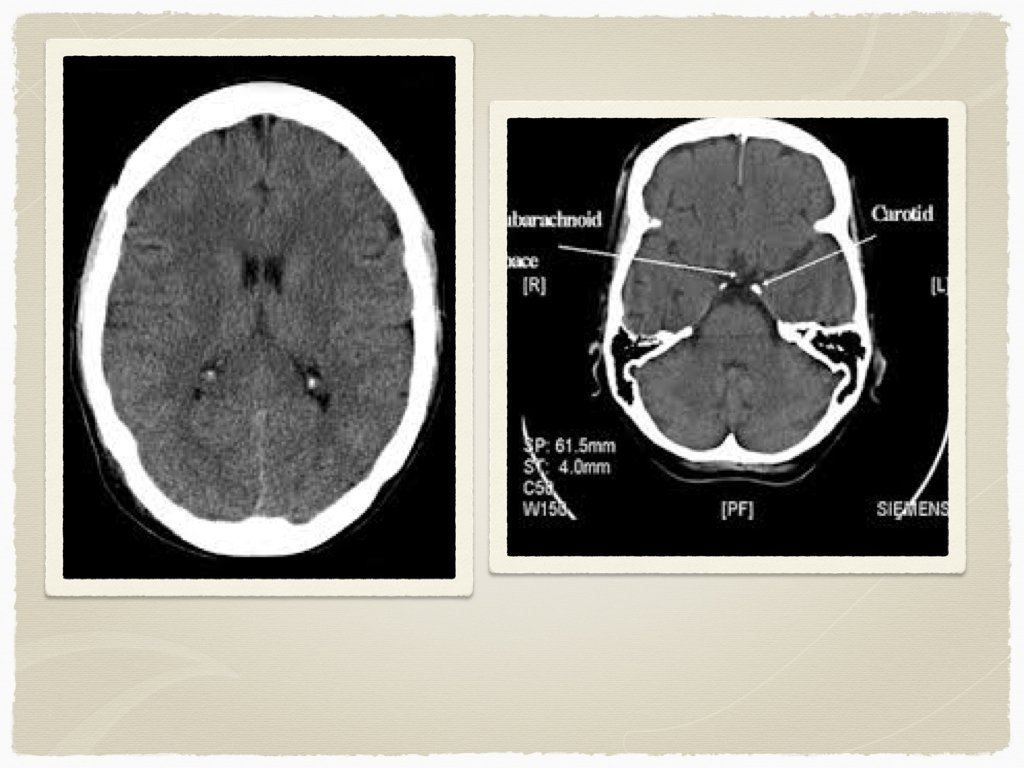

Outside of the window for TPA - Diagnosis CT head: findings? early vs late findings?

Diagnostics CT is the initial test of choice In sentinel bleed for aneurysmal SAH, can be negative LP to follow if suspicion Lab work: INR Troponin ECG